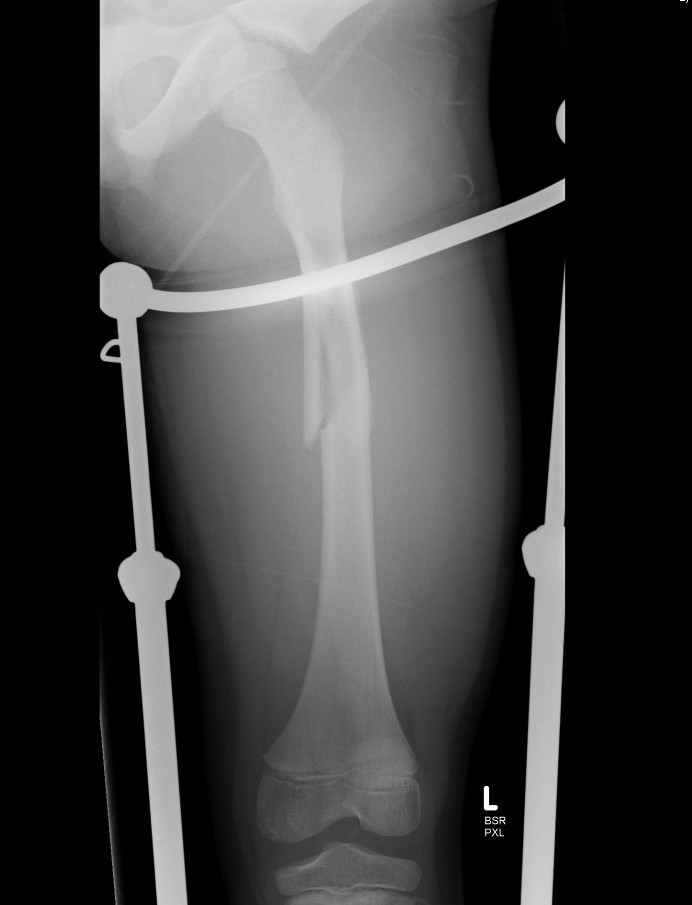

External Fixation

Indication

open wounds as temporary stabiliser

Complications

- pin site infection

- malunion

- refracture post removal